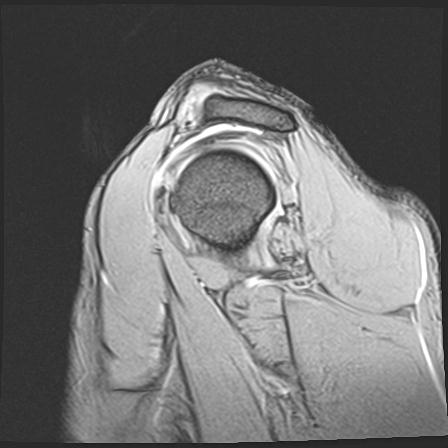

60058 3/9 11/4 右肩 2R+MRI 73歳男性 肩腱板損傷